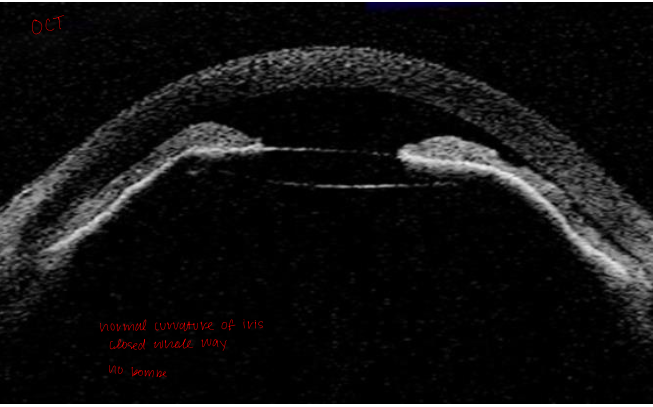

Case 8 anterior chamber OCT

normal curvature of the iris

angle closed the whole way (periphery and central)

no iris bombe